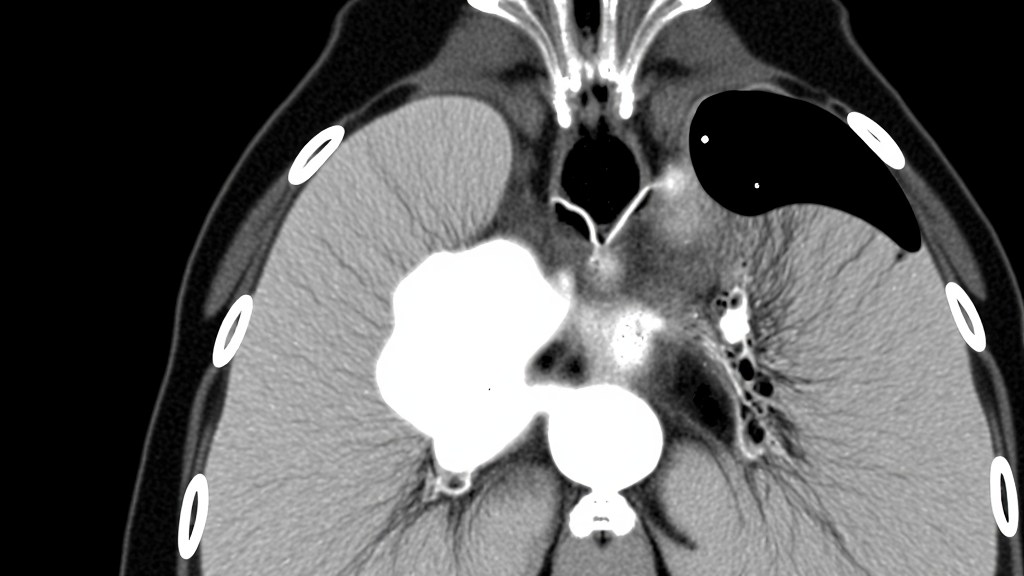

روشهای تشخیص کارسینوم داکتال درجا

ماموگرافی همچنان اصلیترین ابزار برای کشف ضایعات مشکوک است.

بیوپسی سوزنی به پاتولوژیستها کمک میکند تا نوع و درجه ضایعه را مشخص کنند.

در برخی موارد، MRI برای تعیین گستردگی ضایعه مورد استفاده قرار میگیرد، هرچند شواهد قطعی در این زمینه هنوز محدود است.